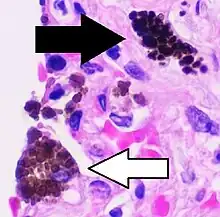

Coal dust is not as fibrogenic as silica dust.[12] Coal dust that enters the lungs can neither be destroyed nor removed by the body. The particles are engulfed by resident alveolar macrophages or interstitial macrophages and remain in the lungs, residing in the connective tissue or pulmonary lymph nodes. Coal dust provides a sufficient stimulus for the macrophage to release various products, including enzymes, cytokines, oxygen radicals, and fibroblast growth factors,[13] which are important in the development of inflammation and fibrosis in BLD. Aggregations of carbon-laden macrophages can be visualized under a microscope as granular, black areas. In serious cases, the lung may grossly appear black. These aggregations can cause inflammation and fibrosis, as well as the formation of nodular lesions within the lungs. The centers of dense lesions may become necrotic due to ischemia, leading to large cavities within the lung.

Simple BLD is marked by the presence of 1–2 mm (0.039–0.079 in) nodular aggregations of anthracotic macrophages, supported by a fine collagen network, within the lungs. Those 1–2 mm in diameter are known as coal macules, with larger aggregations known as coal nodules. These structures occur most frequently around the initial site of coal dust accumulation—the upper regions of the lungs around respiratory bronchioles.[4] The coal macule is the basic pathological feature of BLD and has a surrounding area of enlargement of the airspace, known as focal emphysema.[14][15] Focal emphysema extends into progressive centrilobular emphysema. Less commonly a variant of panacinar emphysema develops.[16]

Continued exposure to coal dust following the development of simple BLD may progress to complicated BLD with progressive massive fibrosis (PMF), wherein large masses of dense fibrosis develop, usually in the upper lung zones, measuring greater than 1 cm (0.39 in) in diameter, with accompanying decreased lung function. These cases generally require a number of years to develop. Grossly, the lung itself appears blackened. Pathologically, these consist of fibrosis with haphazardly-arranged collagen and many pigment-laden macrophages and abundant free pigment. Radiographically, BLD can appear strikingly similar to silicosis. In simple BLD, small rounded nodules predominate, tending to first appear in the upper lung zones. The nodules may coalesce and form large opacities (>1 cm), characterizing complicated BLD, or PMF.